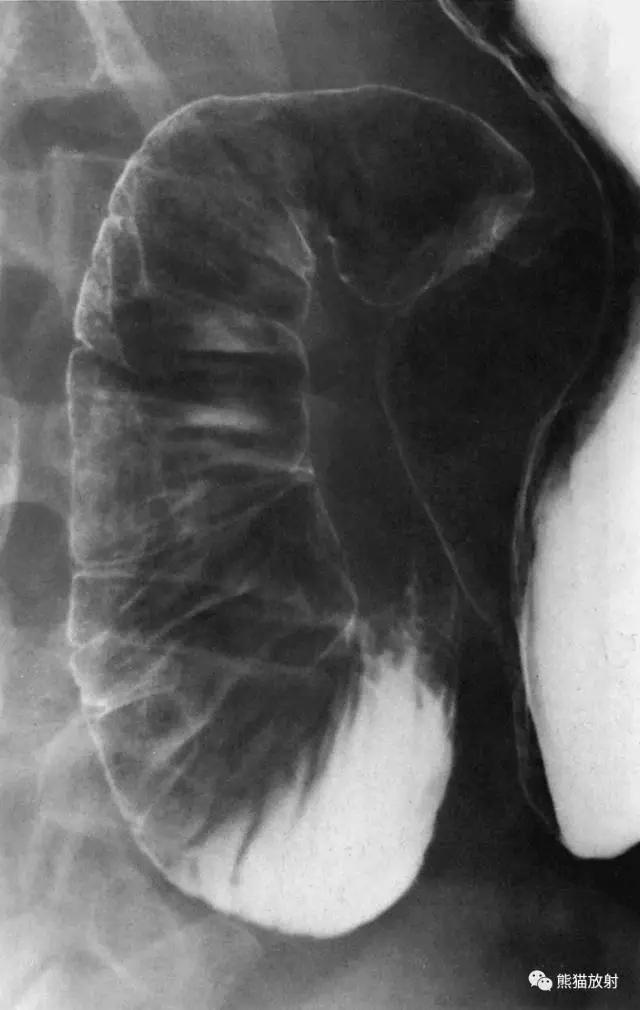

9 Spot Film of the Ileocecal Region 回盲部( 点片 )

1 Haustra of the colon 结肠袋,2 Ascending colon 升结肠,3 Ileum 回肠,4 Ileocecal valve 回盲瓣,5 Terminal ileum 末端回肠,6 Cecum 盲肠